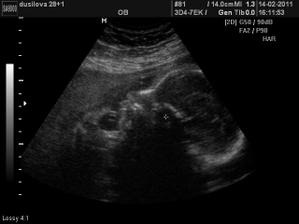

Ve 28tt nám paní doktorka na 3D ukázala krásnýho chlapečka i s jeho pýchou 🙂 Na 99,9% čekáme chlapečka - Tadeáška. Jsem hrozně moc šťastná, že nám vyšlo to co jsme od začátku chtěli - mít starší dcerku a mladšího syna! Tak teď už to jen zdárně doklepat do konce 😀